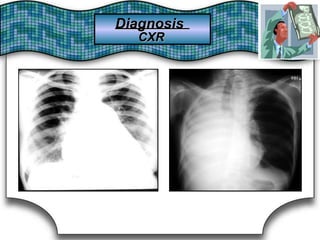

Chest X Ray (CXR)X Ray (CXR)Chest

Chest RadiographRadiographChest Suggestive DiagnosisSuggestive Diagnosis

Cardiomegaly, increasedincreasedCardiomegaly,

pulmonary vascular distributiondistributionpulmonary vascular

Chronic heartheart failure,failure, mitralmitral valve stenosisvalve stenosisChronic

Cavitary lesionsCavitary lesions Lung abscess, TB,TB, necrotizing carcinomanecrotizing carcinomaLung abscess,

Diffuse alveolar infiltratesinfiltratesDiffuse alveolar Chronic heartheart failure,failure, pulmonary edema,pulmonary edema, aspirationaspirationChronic

Hilar adenopathy oradenopathy or massmassHilar Carcinoma, metastaticmetastatic disease,disease, infectioninfectionCarcinoma,

HyperinflationHyperinflation COPDCOPD

Lobar oror segmentalsegmental infiltratesinfiltratesLobar Pneumonia, thromboembolism, obstructing carcinomathromboembolism, obstructing carcinomaPneumonia,

Mass lesion,lesion, nodules,nodules, granulomasgranulomasMass

Carcinoma,

granulomatosis,

metastatic disease, Wegener's

vasculitides

Carcinoma, metastatic disease, Wegener's

septic embolism,granulomatosis, septic embolism, vasculitides

Patchy alveolar infiltratesinfiltratesPatchy alveolar

Bleeding disorders, idiopathic pulmonaryBleeding disorders, idiopathic pulmonary

hemosiderosis, Goodpasture's syndromesyndromehemosiderosis, Goodpasture's